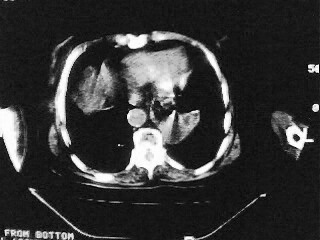

女,79,咳 嗽月余,无其它不适

后纵隔内左心房至肝左叶后方椎体中线偏左巨大软组织包块,其壁均匀比较薄,其内可见宽气液平。

考虑食管裂孔疝。建议钡餐检查